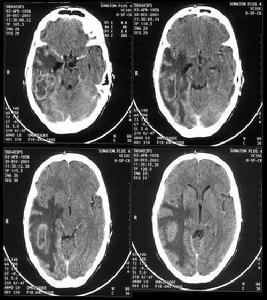

因枕葉較小,只限於枕葉之腫瘤比較少見。腫瘤常壓迫腦室枕角,使枕角變窄或封閉,但必須與正常腦室變異相鑑別,如屬變異範圍,則側腦室系統無移位表現。枕葉腫瘤較大者,常突入側腦室三角區或第三腦室後部,腫瘤侵犯頂枕顳可見側腦室體、三角區、顳解充盈缺損,第三腦室向前推壓。4.腦血管造影

枕葉腫瘤的腦血管造影表現特點是:在前後位像上,大腦前動脈的側移位很輕,走行變化很少。側位像上,可見大腦中動脈主幹及凸面分支向前推擠或部分分散伸直上抬。大腦後動脈顯影時可增粗,末梢分支組相互分開或受壓。深部腫瘤常侵犯小腦幕,故小腦幕切跡動脈可顯影並紆曲增粗。鑑別